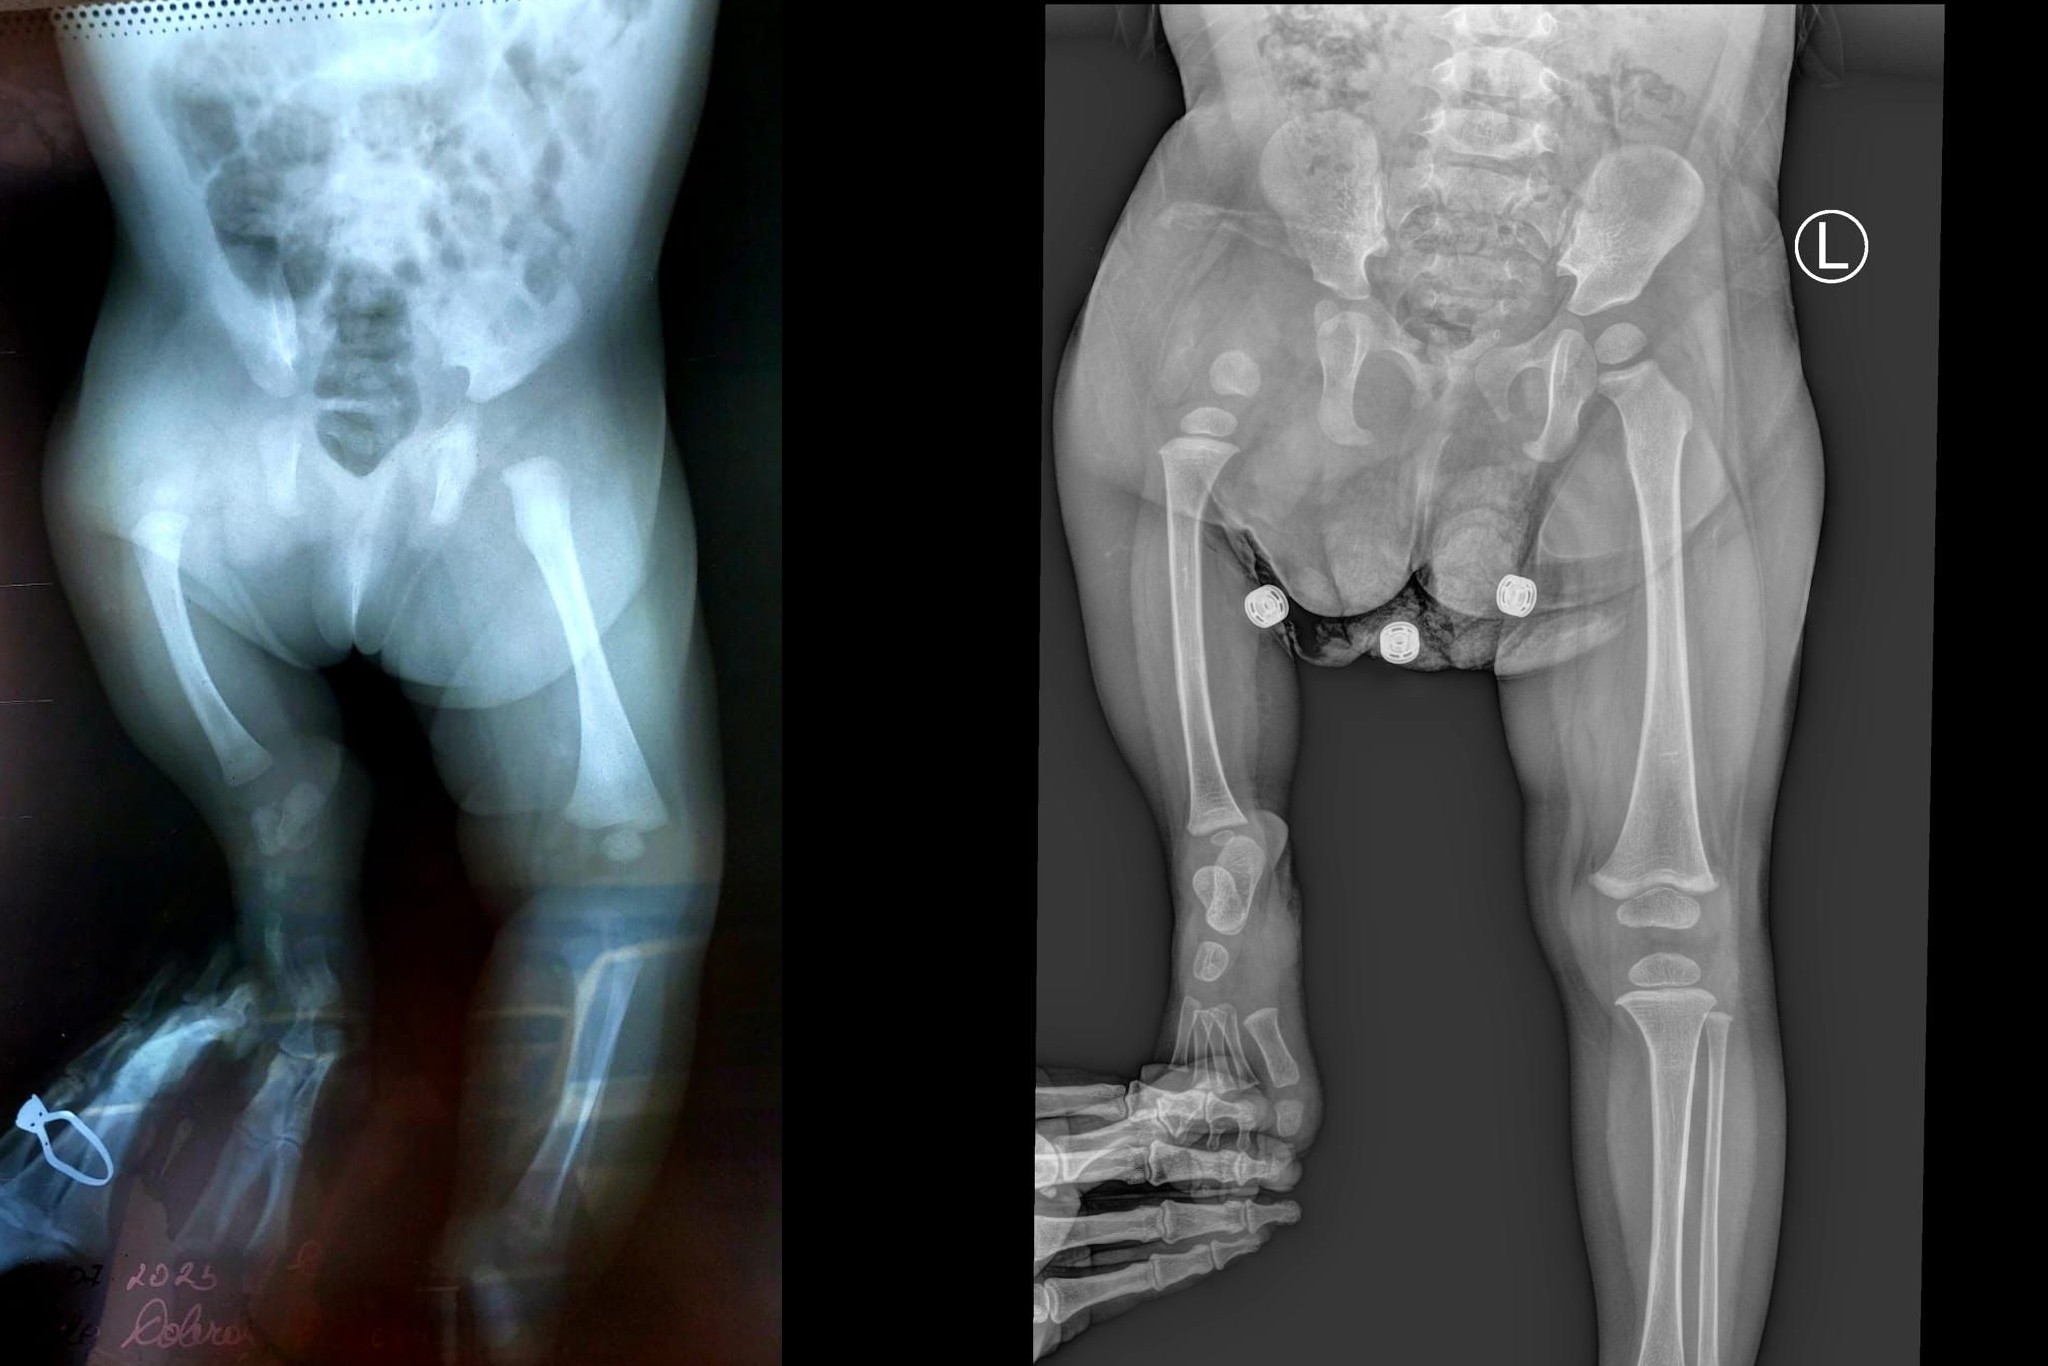

Ilinca s-a născut, în Satu Mare, cu o malformație congenitală gravă la piciorul drept, fiind diagnosticată cu defect femural congenital și hemimelie fibulară dreaptă, cu laba piciorului drept la nivelul genunchiului stâng. În prezent ea poate pășii doar cu ajutorul unei proteze care a fost realizată la Varșovia. Este o fetiță specială datorită dizabilității ei fizice și totodată puternică pentru că reușește să se adapteze nevoilor ei zilnice.